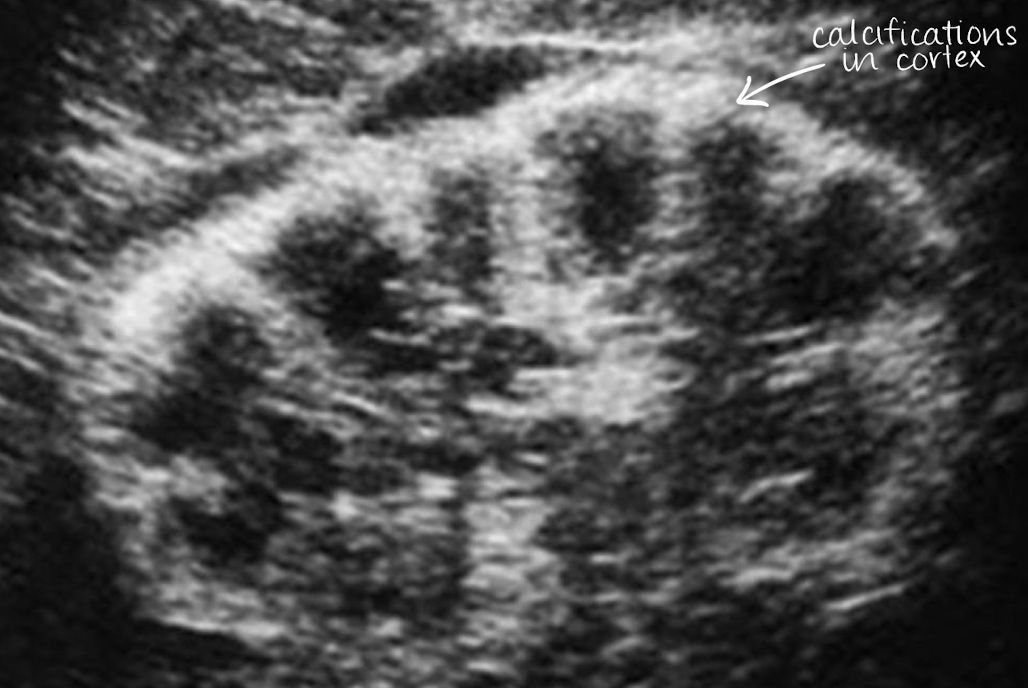

medullary cystic kidney disease (MCKD)

MCKDs include: medullary nephrocalcinosis and cortical nephrocalcinosis

both are inherited disorders that eventually lead to ESRD

SONO: medullary cystic kidney disease (MCKD)

hyperechoic calyces with or without stones

??

medullary cystic kidney disease

calcium deposits in calyces

medullary nephrocalcinosis (medullary cystic kidney disease)

calcium deposits in medulla (heart-shaped ♥)

cortical nephrocalcinosis (medullary cystic kidney disease)

calcium deposits in cortex